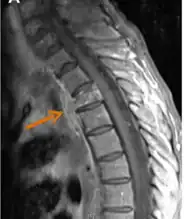

The diagnosis of actinomycosis can be a difficult one to make. In addition to microbiological examinations, magnetic resonance imaging and immunoassays may be helpful.[12]

Contrast-enhanced magnetic resonance images showing contiguous spread of pulmonary actinomycosis to the spine -